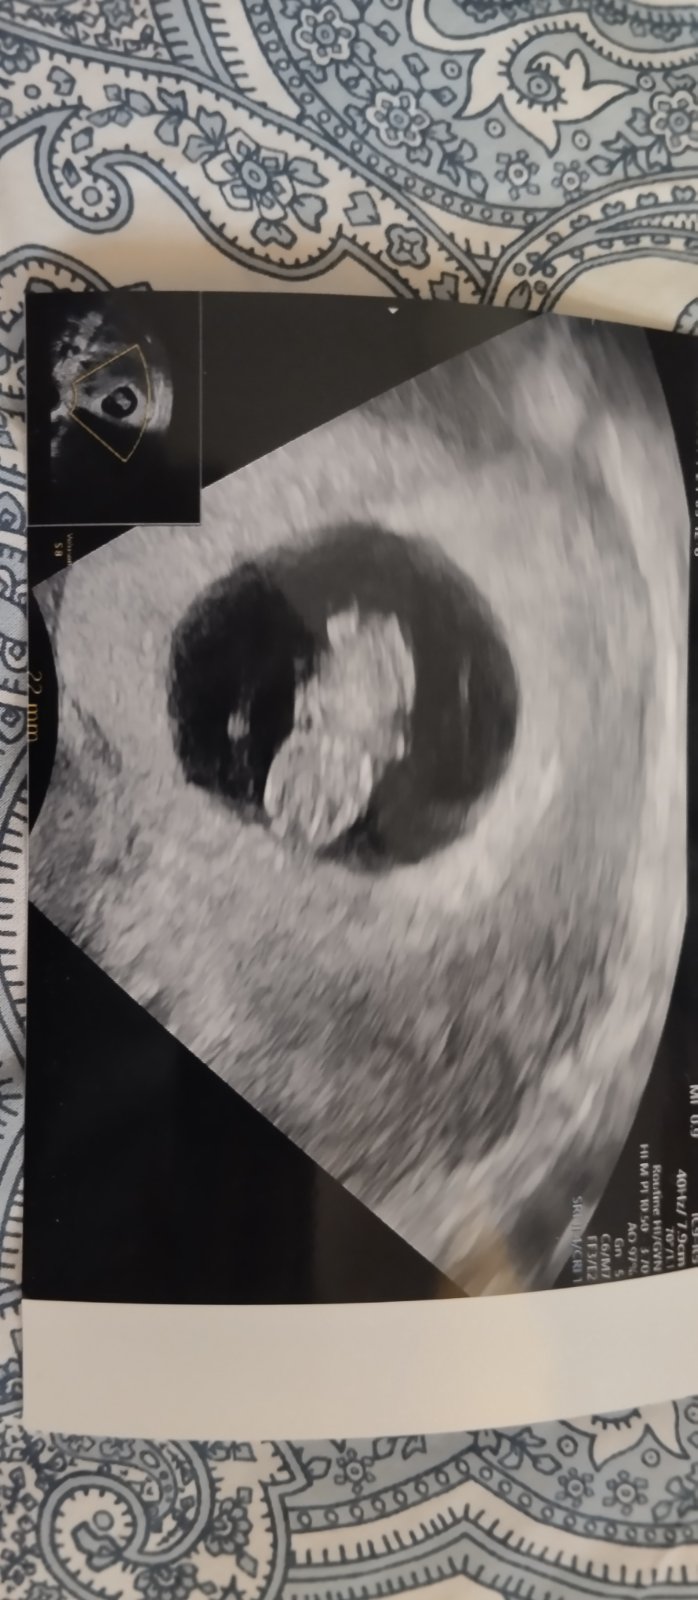

@aquenka já jsem byla dneska na kontrole a všechny bylo v pořádku 🍀 dostala jsem i fotečku